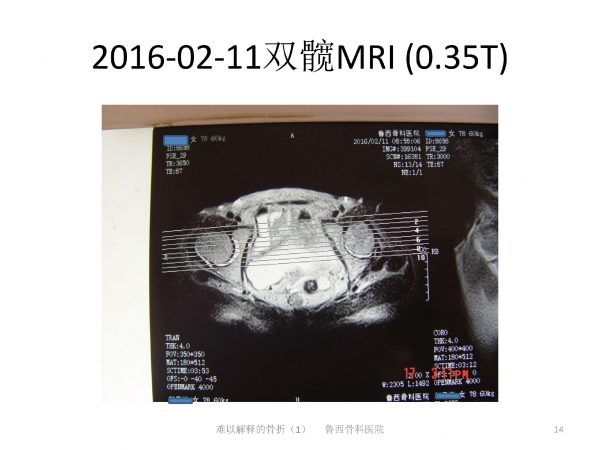

导语:在日常生活中,因老年人普遍存在骨质疏松的问题,滑倒很容易造成髋部骨折。90%的老年人发生髋部骨折多因摔倒引起。然而有些骨折完全没有外伤,前驱疼痛,属于不典型骨折。来自鲁西骨科医院的王书军医师、段玉民医师,为我们带来一例“难以解释的骨折”病例,并做了初步探讨。请详见下文分解。